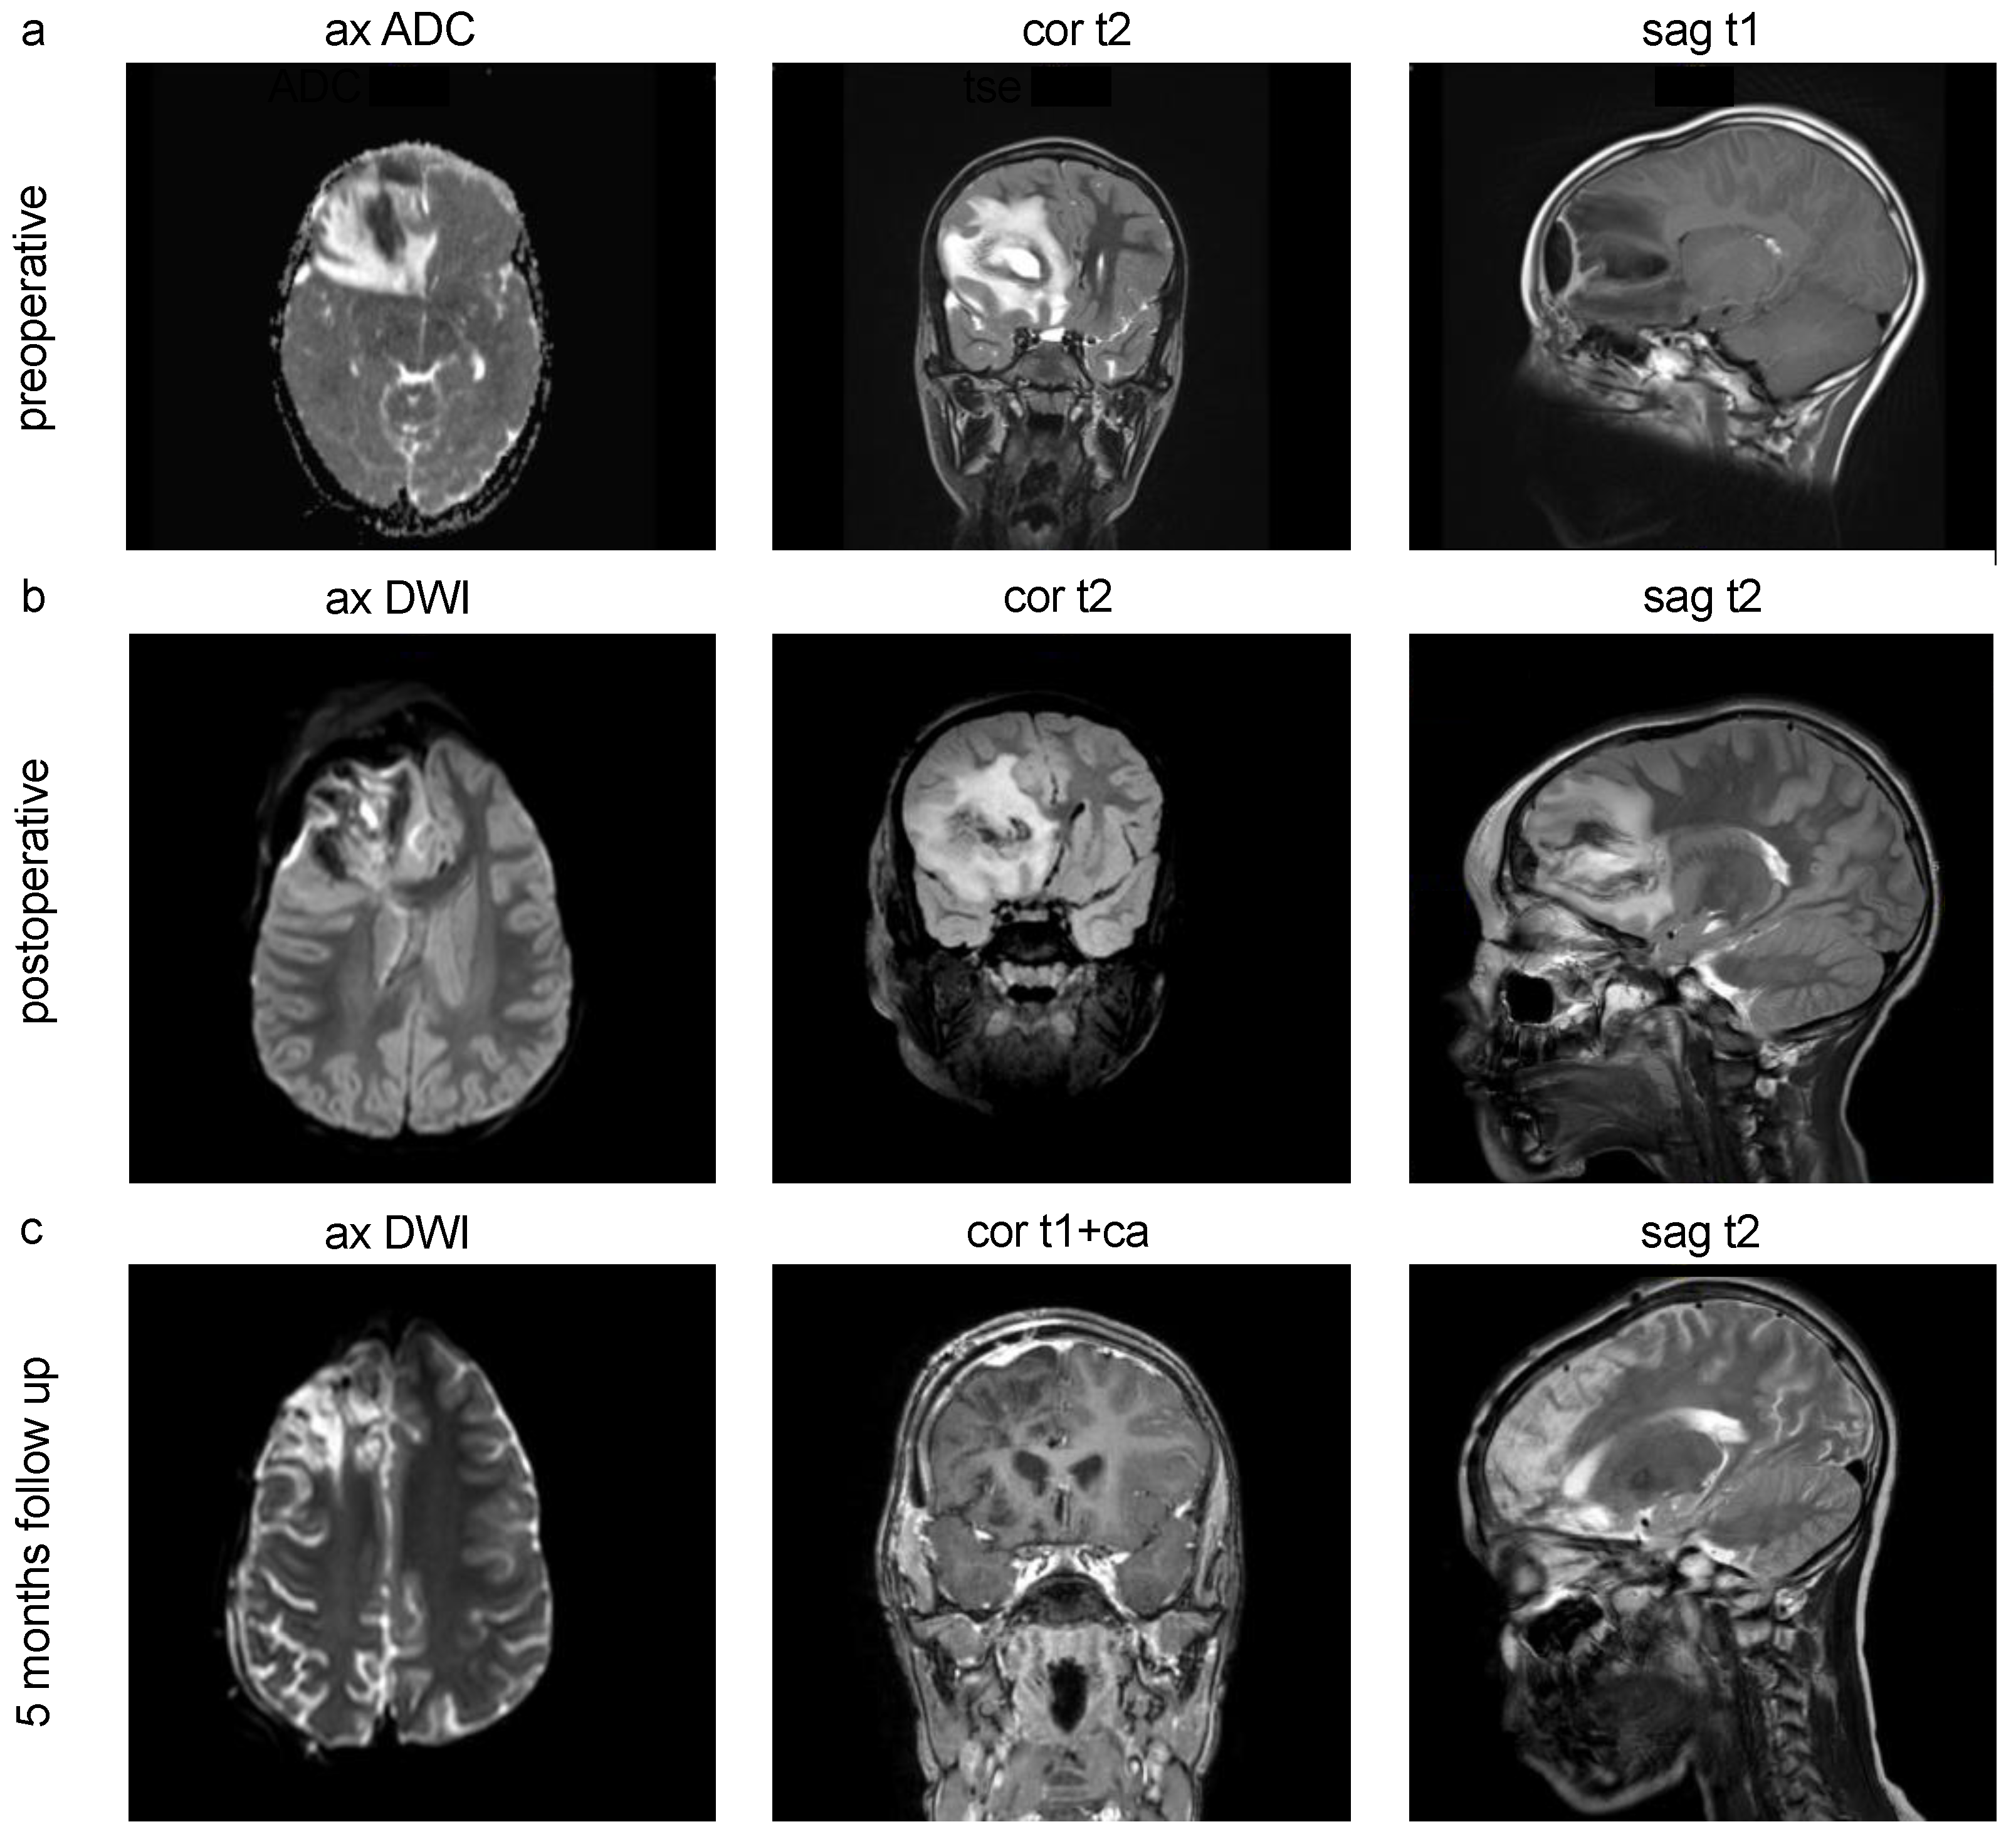

cMRI Imaging of pediatric intracranial abscesses. (a) Preoperative MRI scans of a 10-year-old male patient with pansinusitis and streptococcus anginosus infection, frontal and frontobasal intracranial brain abscess, midline shift subfalcine to the left, compressed right lateral ventricular anterior horn and narrow sulcus drawing with stable spatial conditions. (b) Postoperative control MRI scans after abscess evacuation. (c) 5 months follow up showing no delimitable hygromas or CSF leakage in the condition after neurosurgical hemicraniectomy as well as a known right hemispheric contrast enhancement. ax=axial, cor=coronal, sag=saggital.

In nine cases of eight patients, a total of 13 different pathogens could be isolated. Regarding the intracranial anatomical abscess region, 55.56% were located frontal and frontobasal (

Figure 2), 33.33% temporal and 11.11% cerebellar (11.11%) (

In our cases, abscess drainage was not employed, which is an alternative surgical treatment option used in other neurosurgical centers. The continuation of antibiotic treatment was tailored based on the specific recommendations of the in-house infectious disease guidelines and varied accordingly. Following the mentioned treatment regime, most cases in our analysis showed a favorable outcome (resitutio ad integrum) without a death event and a significant reduction in the follow-up cMRI (

Figure 2c).